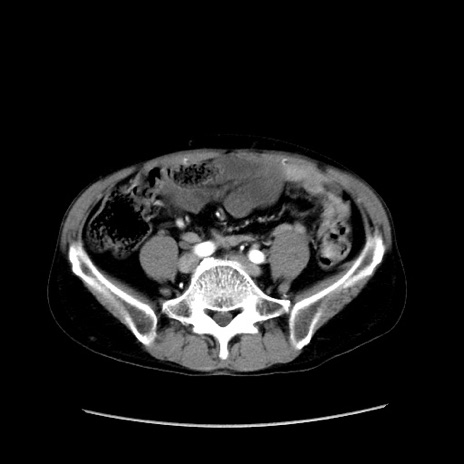

症例37(横断像)

【症例】40歳代 男性

【主訴】腹痛

【現病歴】4時間ほど前に電車に乗車中に臍部上より腹痛出現。徐々に増悪し起立困難となり、救急外来受診。生ものは数日食べていない。今朝お雑煮を食べた。

【身体所見】BT 36.8℃、BP 117/84mmHg、HR 91/min、SpO2 97%、苦悶様、腹部:臍上部広範囲圧痛あり、反跳痛±

【データ】WBC 8100、CRP 0.03